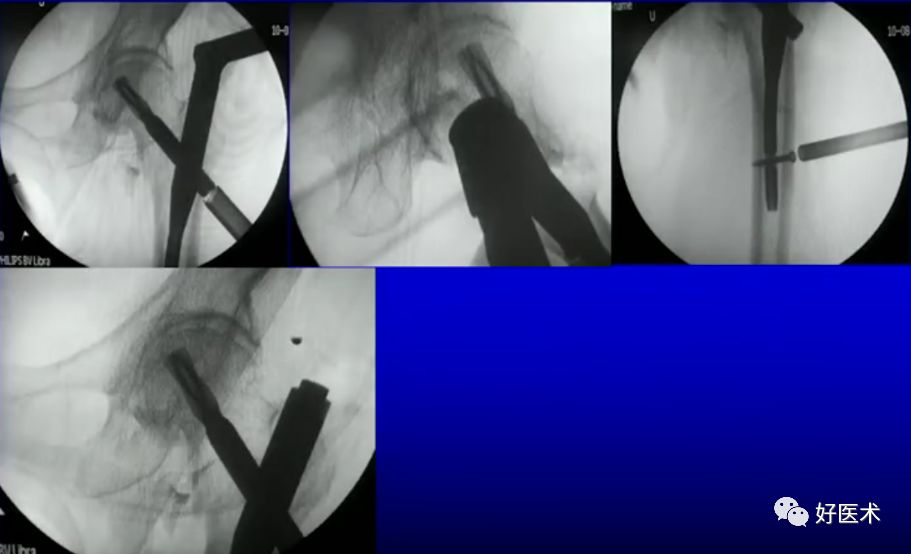

病例一:女 94岁

体表定位与撬棒置顶

撬棒置顶后内收情况

正位进针位置调整情况

主钉插入后的导针正侧位

病例二:女 75岁

术前复位:

定位:

术后: